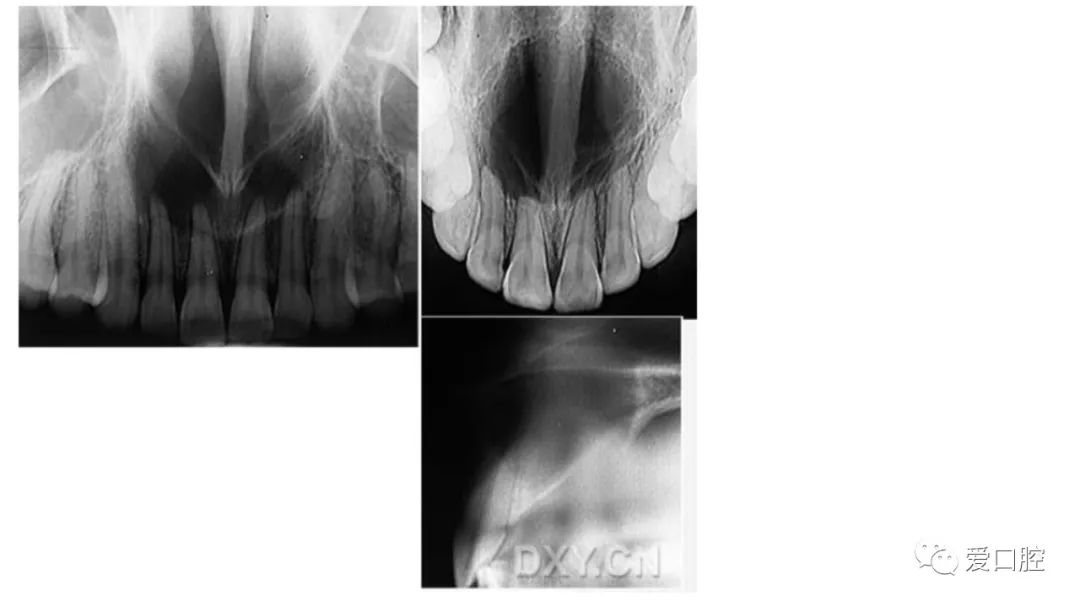

口腔小技巧 | 口腔科常见的病例影像!